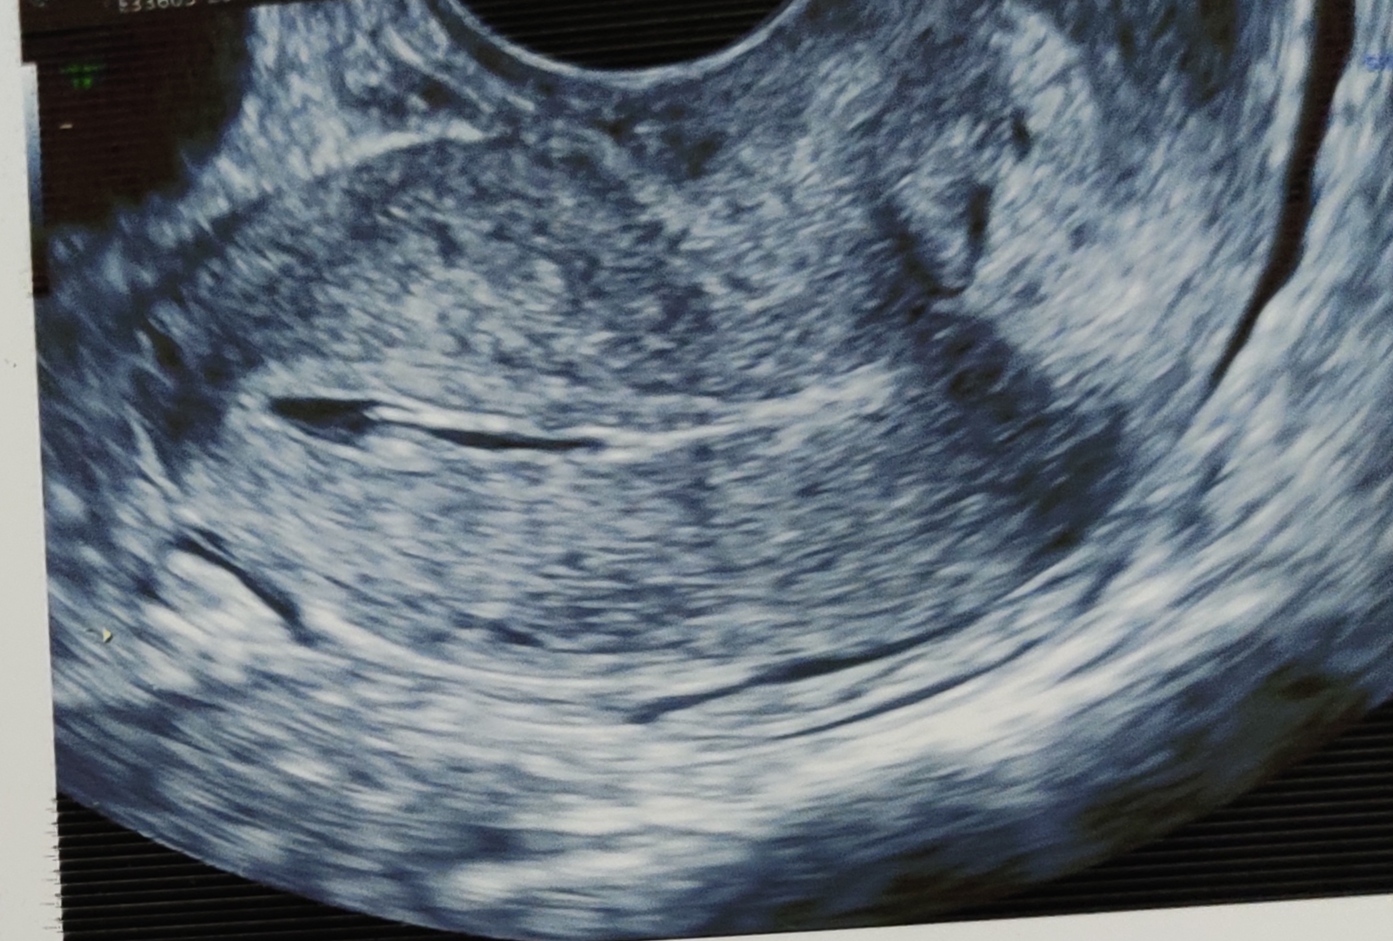

Sub septate uterus

A 26 yrs old woman presented with primary infertility. Sub septate uterus with patent fallopian tubes noted in ultrasound and hysterosalpinogram.